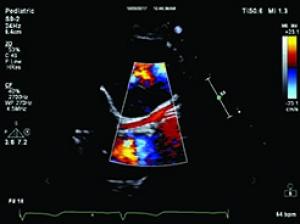

In an environment with growing demand for specialist cardiology services, it is important that health tech innovators support physicians to manage demanding workloads and complex procedures while ensuring the patient remains paramount. Within cardiac ultrasound solutions, recent developments are helping to drive improvements not only in terms of patient outcomes but also the user experience. When it comes to ensuring a confident diagnosis, for clinicians, every diagnostic image and patient moment in the care pathway matters.